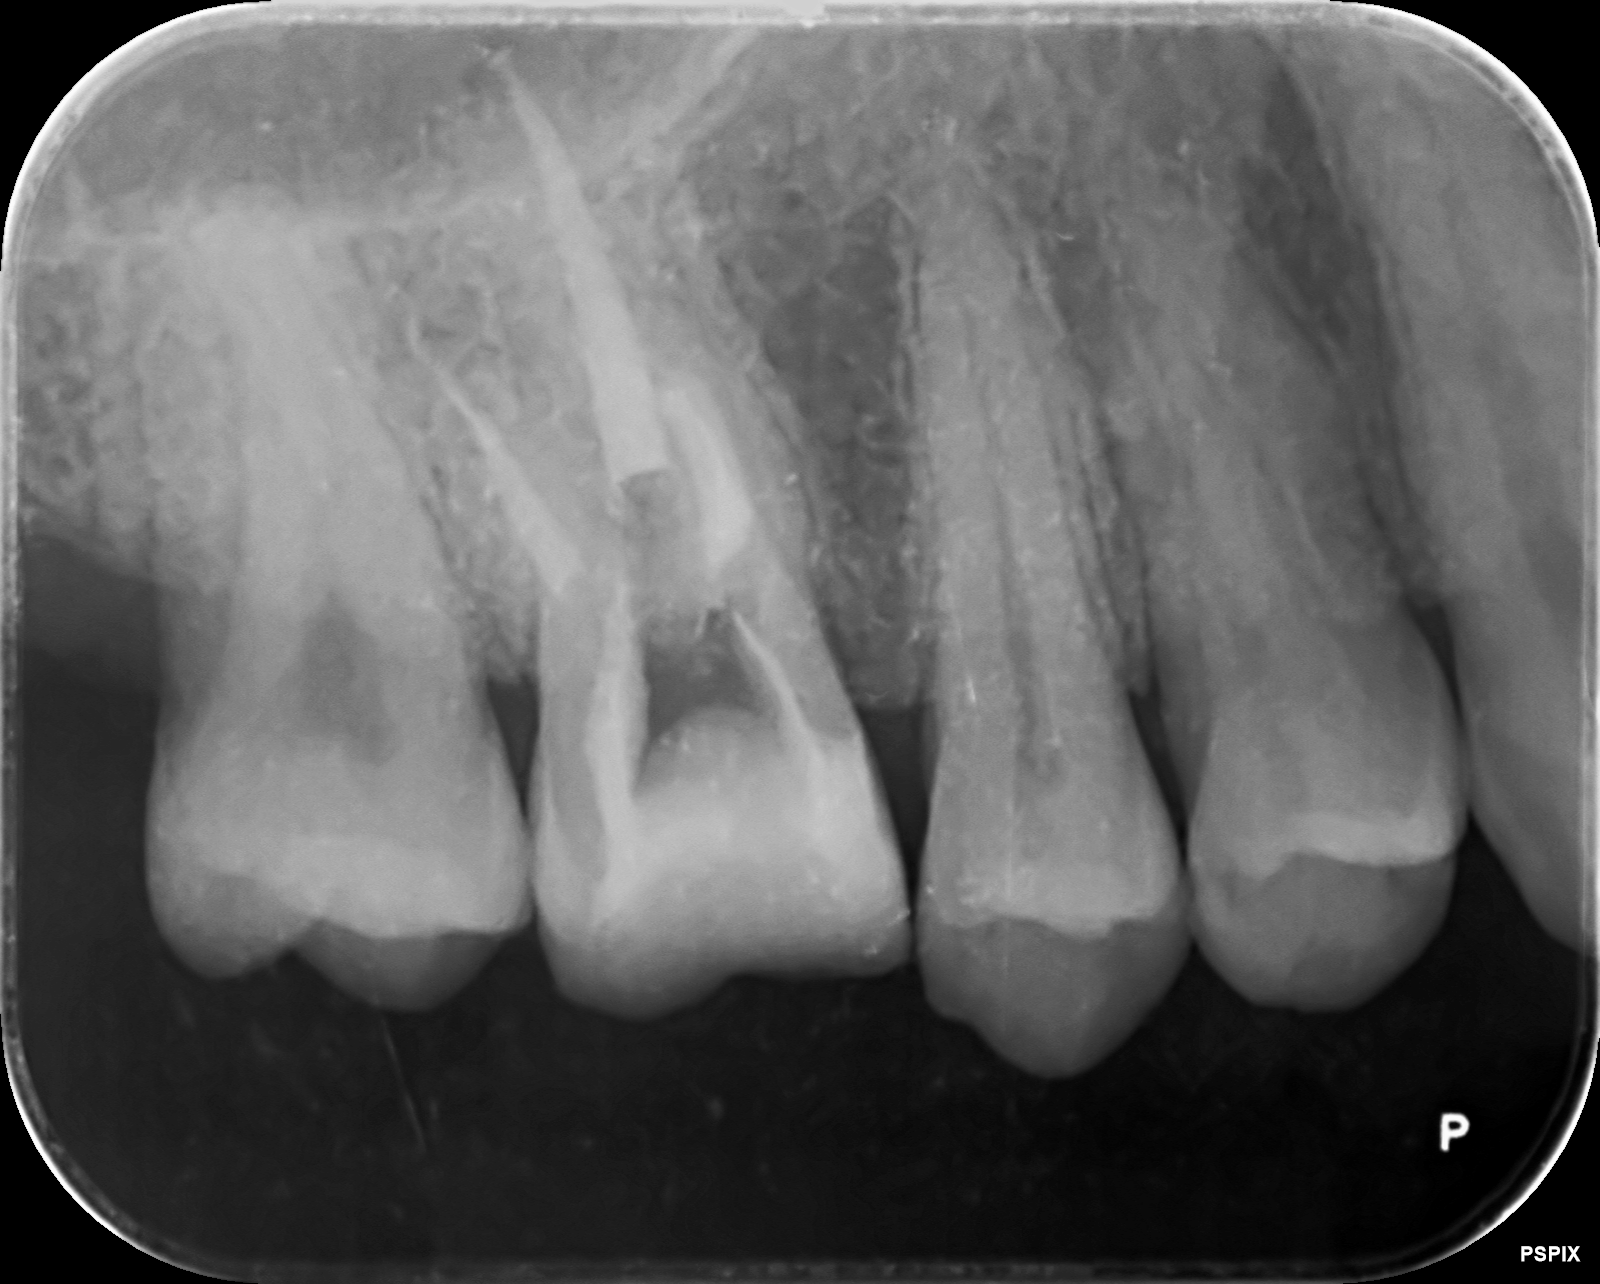

右上6 マイクロエンド

• 治療前

• 治療後

主訴 右上の違和感

リスク・副作用 根尖病変の再発